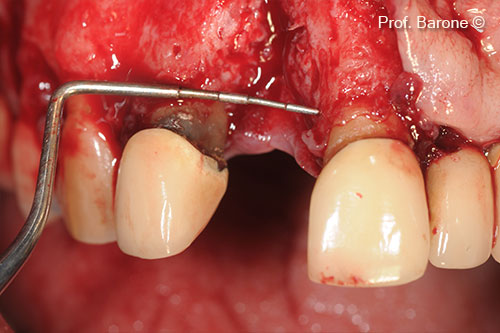

Gờ tăng cường

Chuẩn bị vị trí cấy ghép

Cấy ghép implant vào sống hàm đã được tăng cường